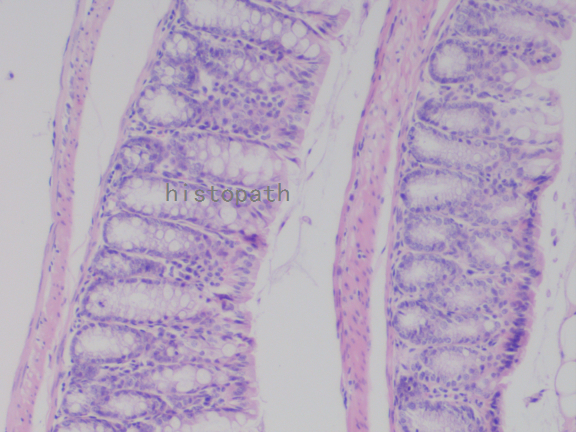

苏木精--伊红染色法(hematoxylin-eosin staining),简称HE染色法,石蜡切片技术里常用的染色法之一。苏木精染液为碱性,主要使细胞核内的染色质与胞质内的核酸着紫蓝色;伊红为酸性染料,主要使细胞质和细胞外基质中的成分着红色。HE染色法使组织学、胚胎学、病理学教学与科研中最基本、使用最广泛的技术方法。

染色结果:

细胞核呈蓝色,细胞质、肌肉、结缔组织、红细胞、嗜曙红颗粒呈不同程度的粉红色。钙盐、软骨基质和各种微生物也可染成蓝色或紫蓝色。核仁呈红色。着色情况不仅与组织或细胞的种类有关,也随其生活周期及病理变化而改变。质量优良的HE染色切片样本,细胞核与细胞质蓝红对比明显,胞核鲜明,核膜及核染色质颗粒均清晰可见。